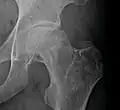

Radiography of avascular necrosis of left femoral head. Man of 45 years with AIDS. -